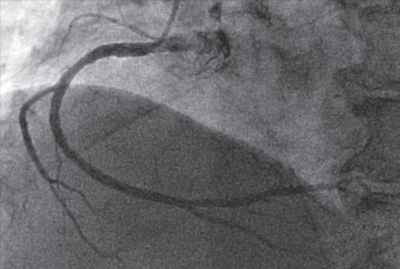

来院時の心電図は完全右脚ブロックで以前と変化はなかった。トレッドミル負荷心電図検査では目標心拍数に達したが、十分な判定ができる所見は得られなかった。冠動脈造影検査で、左前下行枝に50~75%程度の狭窄病変を認めた。矢印は病変部を示す。血行再建術の適応と考えられた。